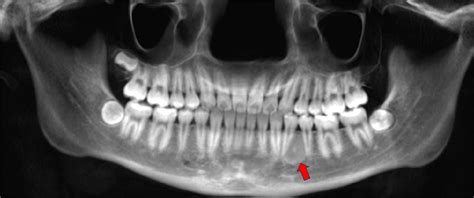

Los exámenes radiográficos (Panorámica, Periapicales y Oclusal) revelaron una imagen circunscrita radiolúcida, unilocular con focos radioopacos, presentándose desde el canino superior (1.3) hasta la región de tuberosidad maxilar y reabsorción radicular en los dientes 1.3 y 1.4.

Radiológicamente el FOC se presenta como áreas radiolúcidas o mixtas en distintos grados. Se manifiesta como una lesión unilocular o multilocular bien delimitada, en cuyo interior podemos encontrar cantidades variables de material radiopaco. Pudiendo también presentar reabsorción radicular y desplazamiento de raíces vecinas.

En el caso presentado los hallazgos radiográficos fueron compatibles con los descritos en la literatura.